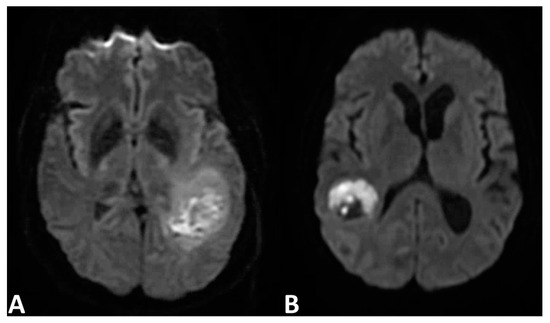

4.1. Diffusion-Weighted Imaging—Measurement of Apparent Diffusion Coefficient

4.2. Diffusion-Weighted Imaging—Exponential Measurements